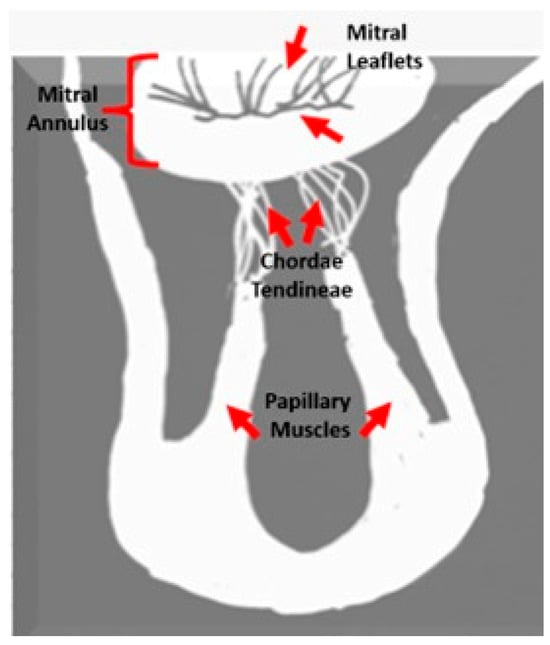

| MAD | Mitral annular disjunction |

| MVP | Mitral annular Prolapses |

| MR | Mitral Regurgitation |